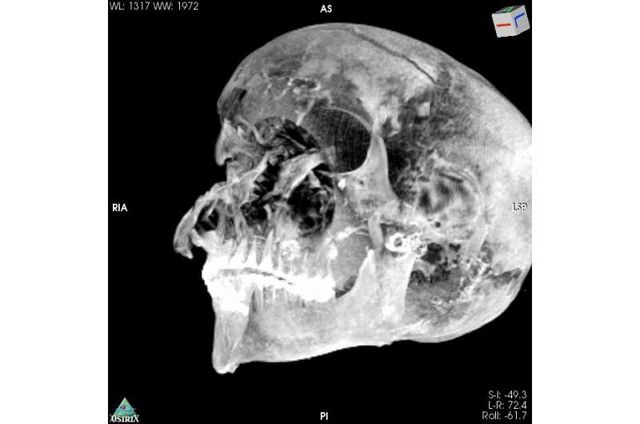

Комп'ютерна томографія єгипетської мумії дозволила встановити причину смерті фараона Секененра Таа II, що правив приблизно в 1569-1554 роках до нашої ери.

Поганий стан мумії наводив на думку, що бальзамування проводилося в поспіху, далеко від королівської майстерні муміфікації. Попередні дослідження дозволили виявити сліди травм на черепі. Вчені вважають, що насильницька смерть Секененра спонукала його наступників продовжити боротьбу за об'єднання Єгипту.

Нове дослідження, проведене за допомогою комп'ютерного томографа, дозволило виявити раніше непомічені пошкодження, які бальзамувальникам вдалося майстерно приховати. Це доводить, що муміфікація проводилася в добре обладнаному місці справжніми професіоналами своєї справи. Характер травм підтверджує раніше висунуту версію про полонення в бою.